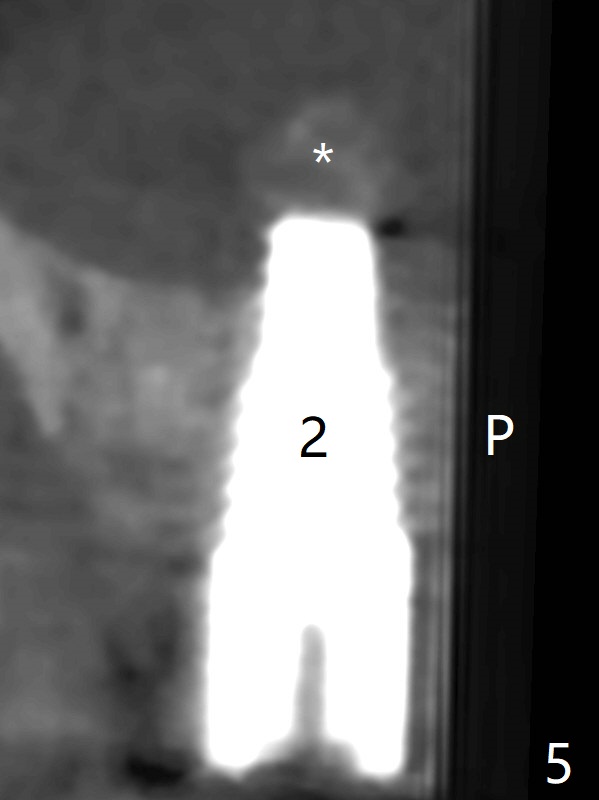

After osteotomy using bone-level implant guide at #4, the crown and abutment at #3 has to be removed to place a 4x14 mm tissue-level dummy implant because of the narrow space of #4 and implant placement angulation (Fig.1). Following initial placement of a final 4x17 mm implant and bone graft (Fig.2 *), the crown and abutment of #3 and the guide are reseated for correct implant trajectory. The guide has to be removed for final depth control. With the same mode, a 5x17 mm tissue-level tap is used at #2 following bone-level osteotomy with guide. A 5x14 mm tissue-level implant is placed with >50 Ncm (later placed deeper), while more bone graft is inserted mesial of #4 implant with a 3.5x5 mm abutment (Fig.3 *). Bone graft is introduced into the sinus using guided sinus lift kit (Fig.4,5 (CT sagittal and coronal sections)) * (D: distal, P: palatal)). The coronal half of the implant at #4 is covered by bone graft (Fig.6 *) buccal (B) and palatal within the deep socket. The implants at #2 and 4 seem to have osteointegrated nearly 5.5 months postop (Fig.7,8 (BW)). A 4.5x5 mm unipost is later placed at #2 with long chamfer margin. It appears that the abutment at #3 is wide. The hex is worn. It changes to a 5.5x7(4) mm one. After abutment adjustment for parallelism, a provisional FPD is fabricated. The latter will be adjusted for papilla formation between implants to reduce food impaction.